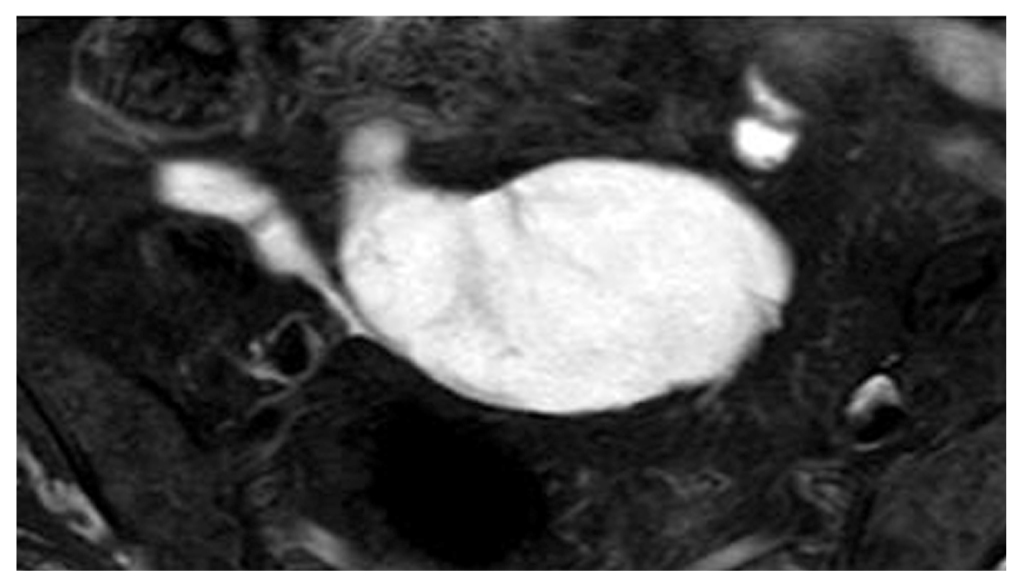

Из анамнеза известно, что в июле 2020 года при диспансерном наблюдении по данным ультразвукового исследования органов брюшной полости у пациентки выявлены кистозное образование малого таза и калькулёзный холецистит. При компьютерной томографии органов брюшной полости с внутривенным контрастированием обнаружены кистозная опухоль червеобразного отростка размером 70×50 мм с наличием кальцинатов в стенке и калькулёзный холецистит (рис. 1). При динамическом наблюдении через 3 года отмечена отрицательная динамика в виде клинической симптоматики и увеличения в размерах кистозной опухоли. Магнитно-резонансная томография органов брюшной полости (апрель 2023 года) показала кистозную опухоль червеобразного отростка размером 106×70 мм с наличием кальцинатов и калькулёзный холецистит (рис. 2).

Рис. 1. Компьютерная томография органов брюшной полости с внутривенным контрастированием: 1 — калькулёзный холецистит; 2 — кистозная опухоль аппендикса диаметром около 7 см.

Fig. 1. A Computed tomography scan of the abdominal organs with intravenous contrast: 1 — calculous cholecystitis; 2 — cystic tumor of the appendix with a diameter of about 7 cm.